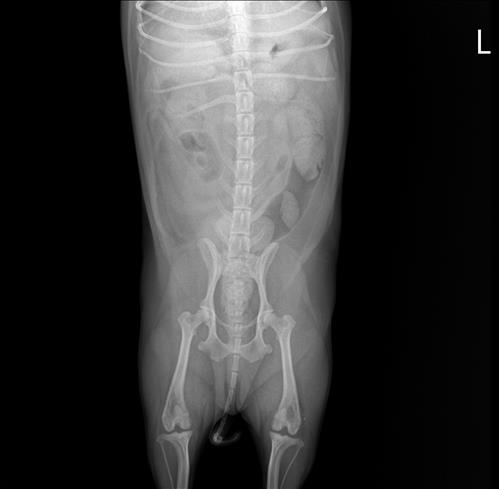

2016년생 10세 8kg 비숑입니다

오른쪽 뒷다리를 서있을째 떨다가 이젠 깽깽이발을 하길래 근처 동물병원을 갔더니 십자인대가 손상됐다고 했어요 파열이 아니라 체중감량하고 약물 처방 해줬다는데 진통제라 치료의 개념은 아니라고 생각하는데 근본적인 치료는 수술이 맞을까요..?